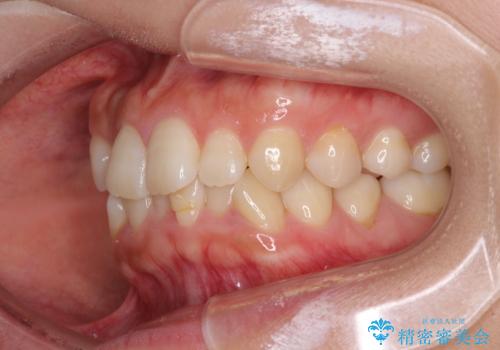

- 前歯のクロスバイトを気にして来院された患者様です。

治療前にお伝えした治療期間は1~1年半でして、1年4か月の期間で終えることができました。